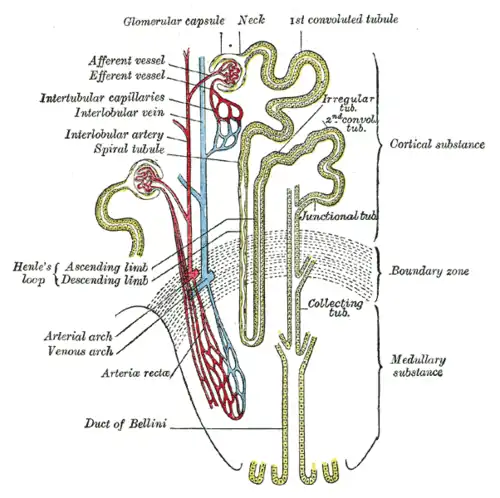

In the kidney

A circuit of fluid in the loop of Henle—an important part of the kidneys—allows for gradual buildup of the concentration of urine in the kidneys, by using active transport on the exiting nephrons (tubules carrying liquid in the process of gradually concentrating the urea). The active transport pumps need only to overcome a constant and low gradient of concentration, because of the countercurrent multiplier mechanism.[4]

Various substances are passed from the liquid entering the nephrons until exiting the loop (See the nephron flow diagram). The sequence of flow is as follows:

- Renal corpuscle: Liquid enters the nephron system at the Bowman's capsule.[5]

- Proximal convoluted tubule: It then may reabsorb urea in the thick descending limb.[6] Water is removed from the nephrons by osmosis (and glucose and other ions are pumped out with active transport), gradually raising the concentration in the nephrons.[7]

- Loop of Henle Descending: The liquid passes from the thin descending limb to the thick ascending limb. Water is constantly released via osmosis.[8] Gradually there is a buildup of osmotic concentration, until 1200 mOsm is reached at the loop tip, but the difference across the membrane is kept small and constant.

- For example, the liquid at one section inside the thin descending limb is at 400 mOsm while outside it is 401. Further down the descending limb, the inside concentration is 500 while outside it is 501, so a constant difference of 1 mOsm is kept all across the membrane, although the concentration inside and outside are gradually increasing.

- Loop of Henle Ascending: after the tip (or 'bend') of the loop, the liquid flows in the thin ascending limb.[9] Salt–sodium Na+ and chloride Cl− ions are pumped out of the liquid[10] gradually lowering the concentration in the exiting liquid, but, using the countercurrent multiplier mechanism, always pumping against a constant and small osmotic difference.

- For example, the pumps at a section close to the bend, pump out from 1000 mOsm inside the ascending limb to 1200 mOsm outside it, with a 200 mOsm across. Pumps further up the thin ascending limb, pump out from 400 mOsm into liquid at 600 mOsm, so again the difference is retained at 200 mOsm from the inside to the outside, while the concentration both inside and outside are gradually decreasing as the liquid flow advances.

- The liquid finally reaches a low concentration of 100 mOsm when leaving the thin ascending limb and passing through the thick one[11]

- Distal convoluted tubule: Once leaving the loop of Henle the thick ascending limb can optionally reabsorb and re increase the concentration in the nephrons.[12]

- Collecting duct: The collecting duct receives liquid between 100 mOsm if no re-absorption is done, to 300 or above if re-absorption was used. The collecting duct may continue raising the concentration if required, by gradually pumping out the same ions as the Distal convoluted tubule, using the same gradient as the ascending limbs in the loop of Henle, and reaching the same concentration.[13]

- Ureter: The liquid urine leaves to the ureter.

- Same principle is used in hemodialysis within artificial kidney machines.